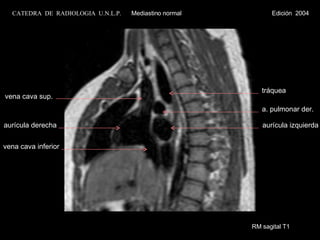

RM sagital T1 aurícula derecha vena cava inferior vena cava sup. aurícula izquierda a. pulmonar der. tráquea CATEDRA  DE  RADIOLOGIA  U.N.L.P.   Mediastino normal  Edición  2004

RM sagital T1aurícula derecha vena cava inferior vena cava sup. aurícula izquierda a. pulmonar der. tráquea CATEDRA DE RADIOLOGIA U.N.L.P. Mediastino normal Edición 2004